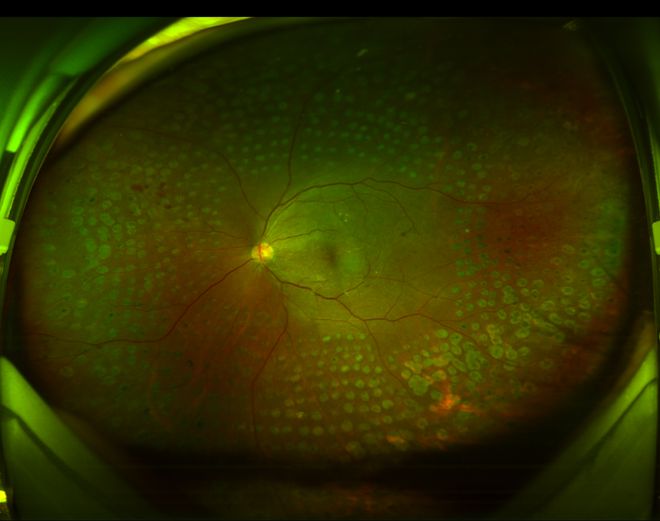

正常眼底

手术后眼底